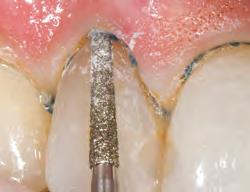

PREPARATION

2. Extend margin subgingivally by cutting partway into knitted cord, which won’t entangle in diamond bur. Remove remnant of cord with an explorer or other instrument. Bleeding is minimal if at all. A small portion of uncut tooth above gingival attachment is preserved to record in impression. If additional retraction is required, repack with appropriately sized cord. Rinse, air dry, and make impression.